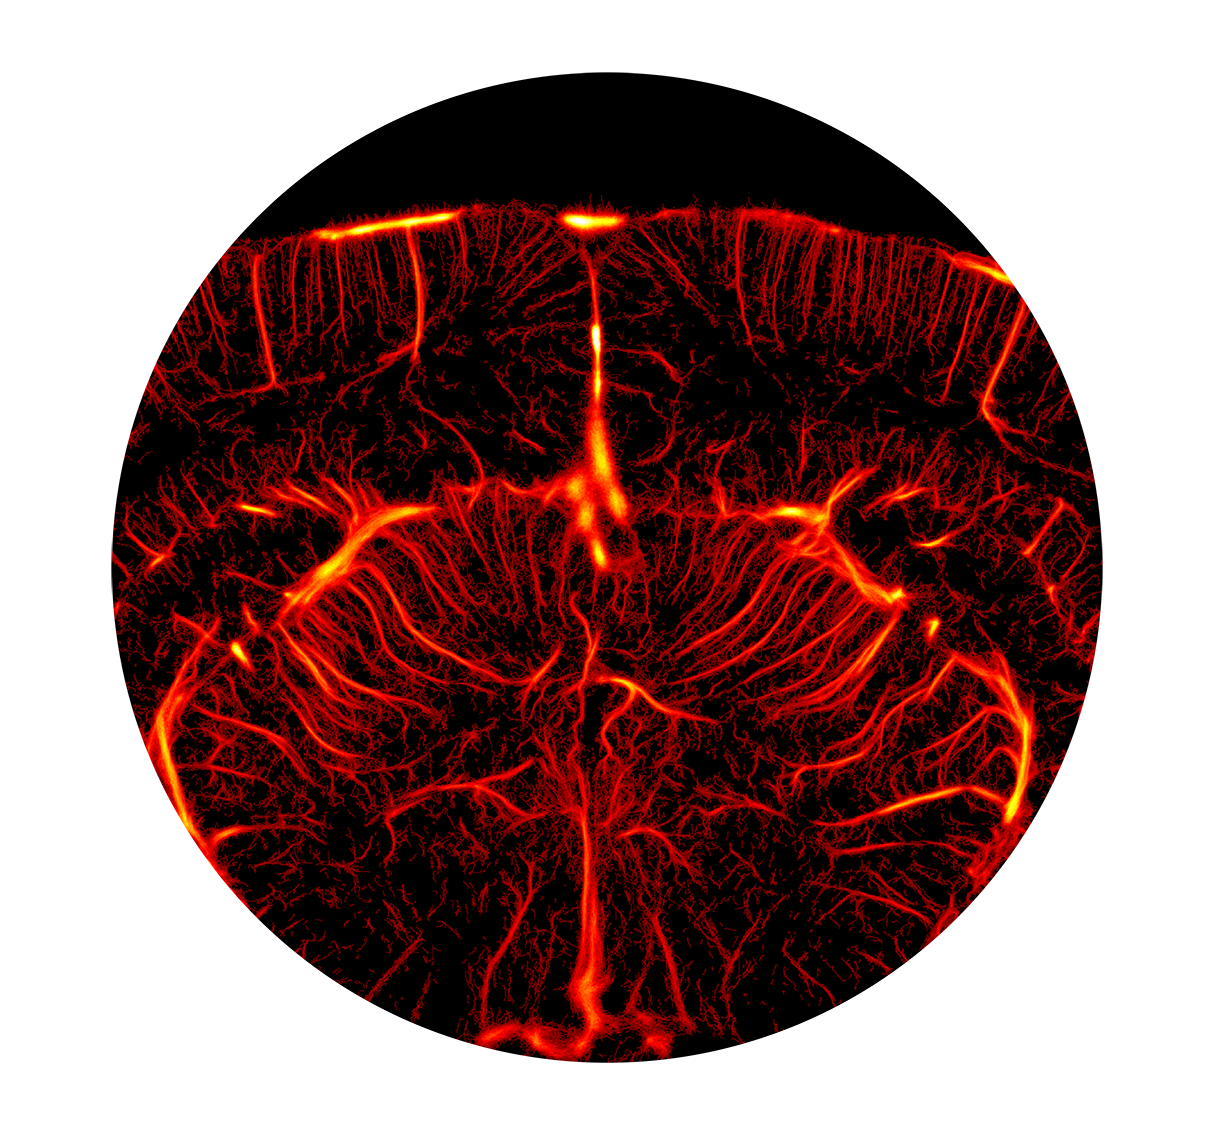

脑/脊髓血流成像

fUSI对血流的高灵敏度,可以快速轻松地呈现全脑血流成像,从主要动脉到小动脉。这种微细血流成像可用于多种研究场景,包括评估阿尔茨海默病和动脉瘤期间血管系统变化,监测卒中的缺血和再灌注,研究脑血流自动调节,以及研究脑肿瘤血管系统对治疗的反应。